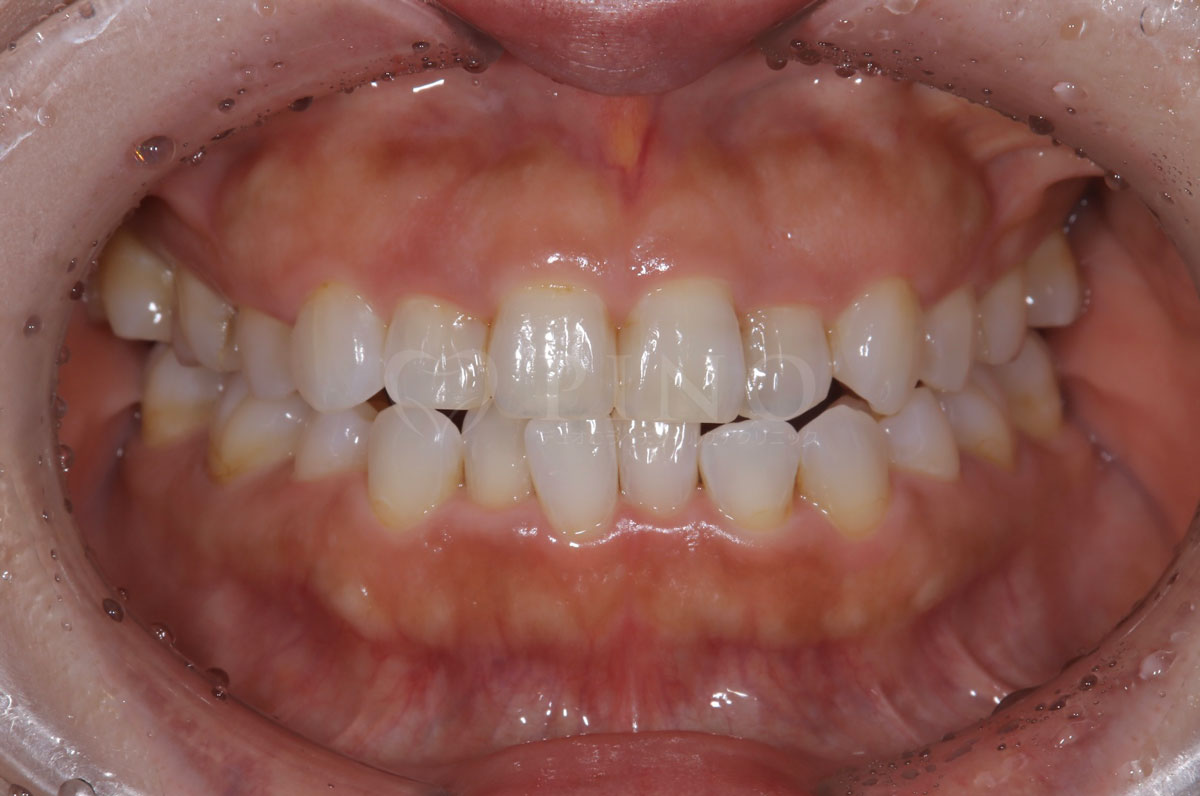

症例3:ワイヤー矯正後の後戻りが気になる(40代女性)

主訴 ワイヤー矯正後の後戻りが気になる 診断名 叢生 治療方法 マウスピース部分矯正 抜歯 なし オルソパルス なし 治療期間 9ヶ月 費用 436,000円 副作用・注意点 矯正後の後戻りを防ぐためリテーナーの使用が必要となる 備考 奥歯に噛み合わせ不良がない場合、部分矯正が適応となる -